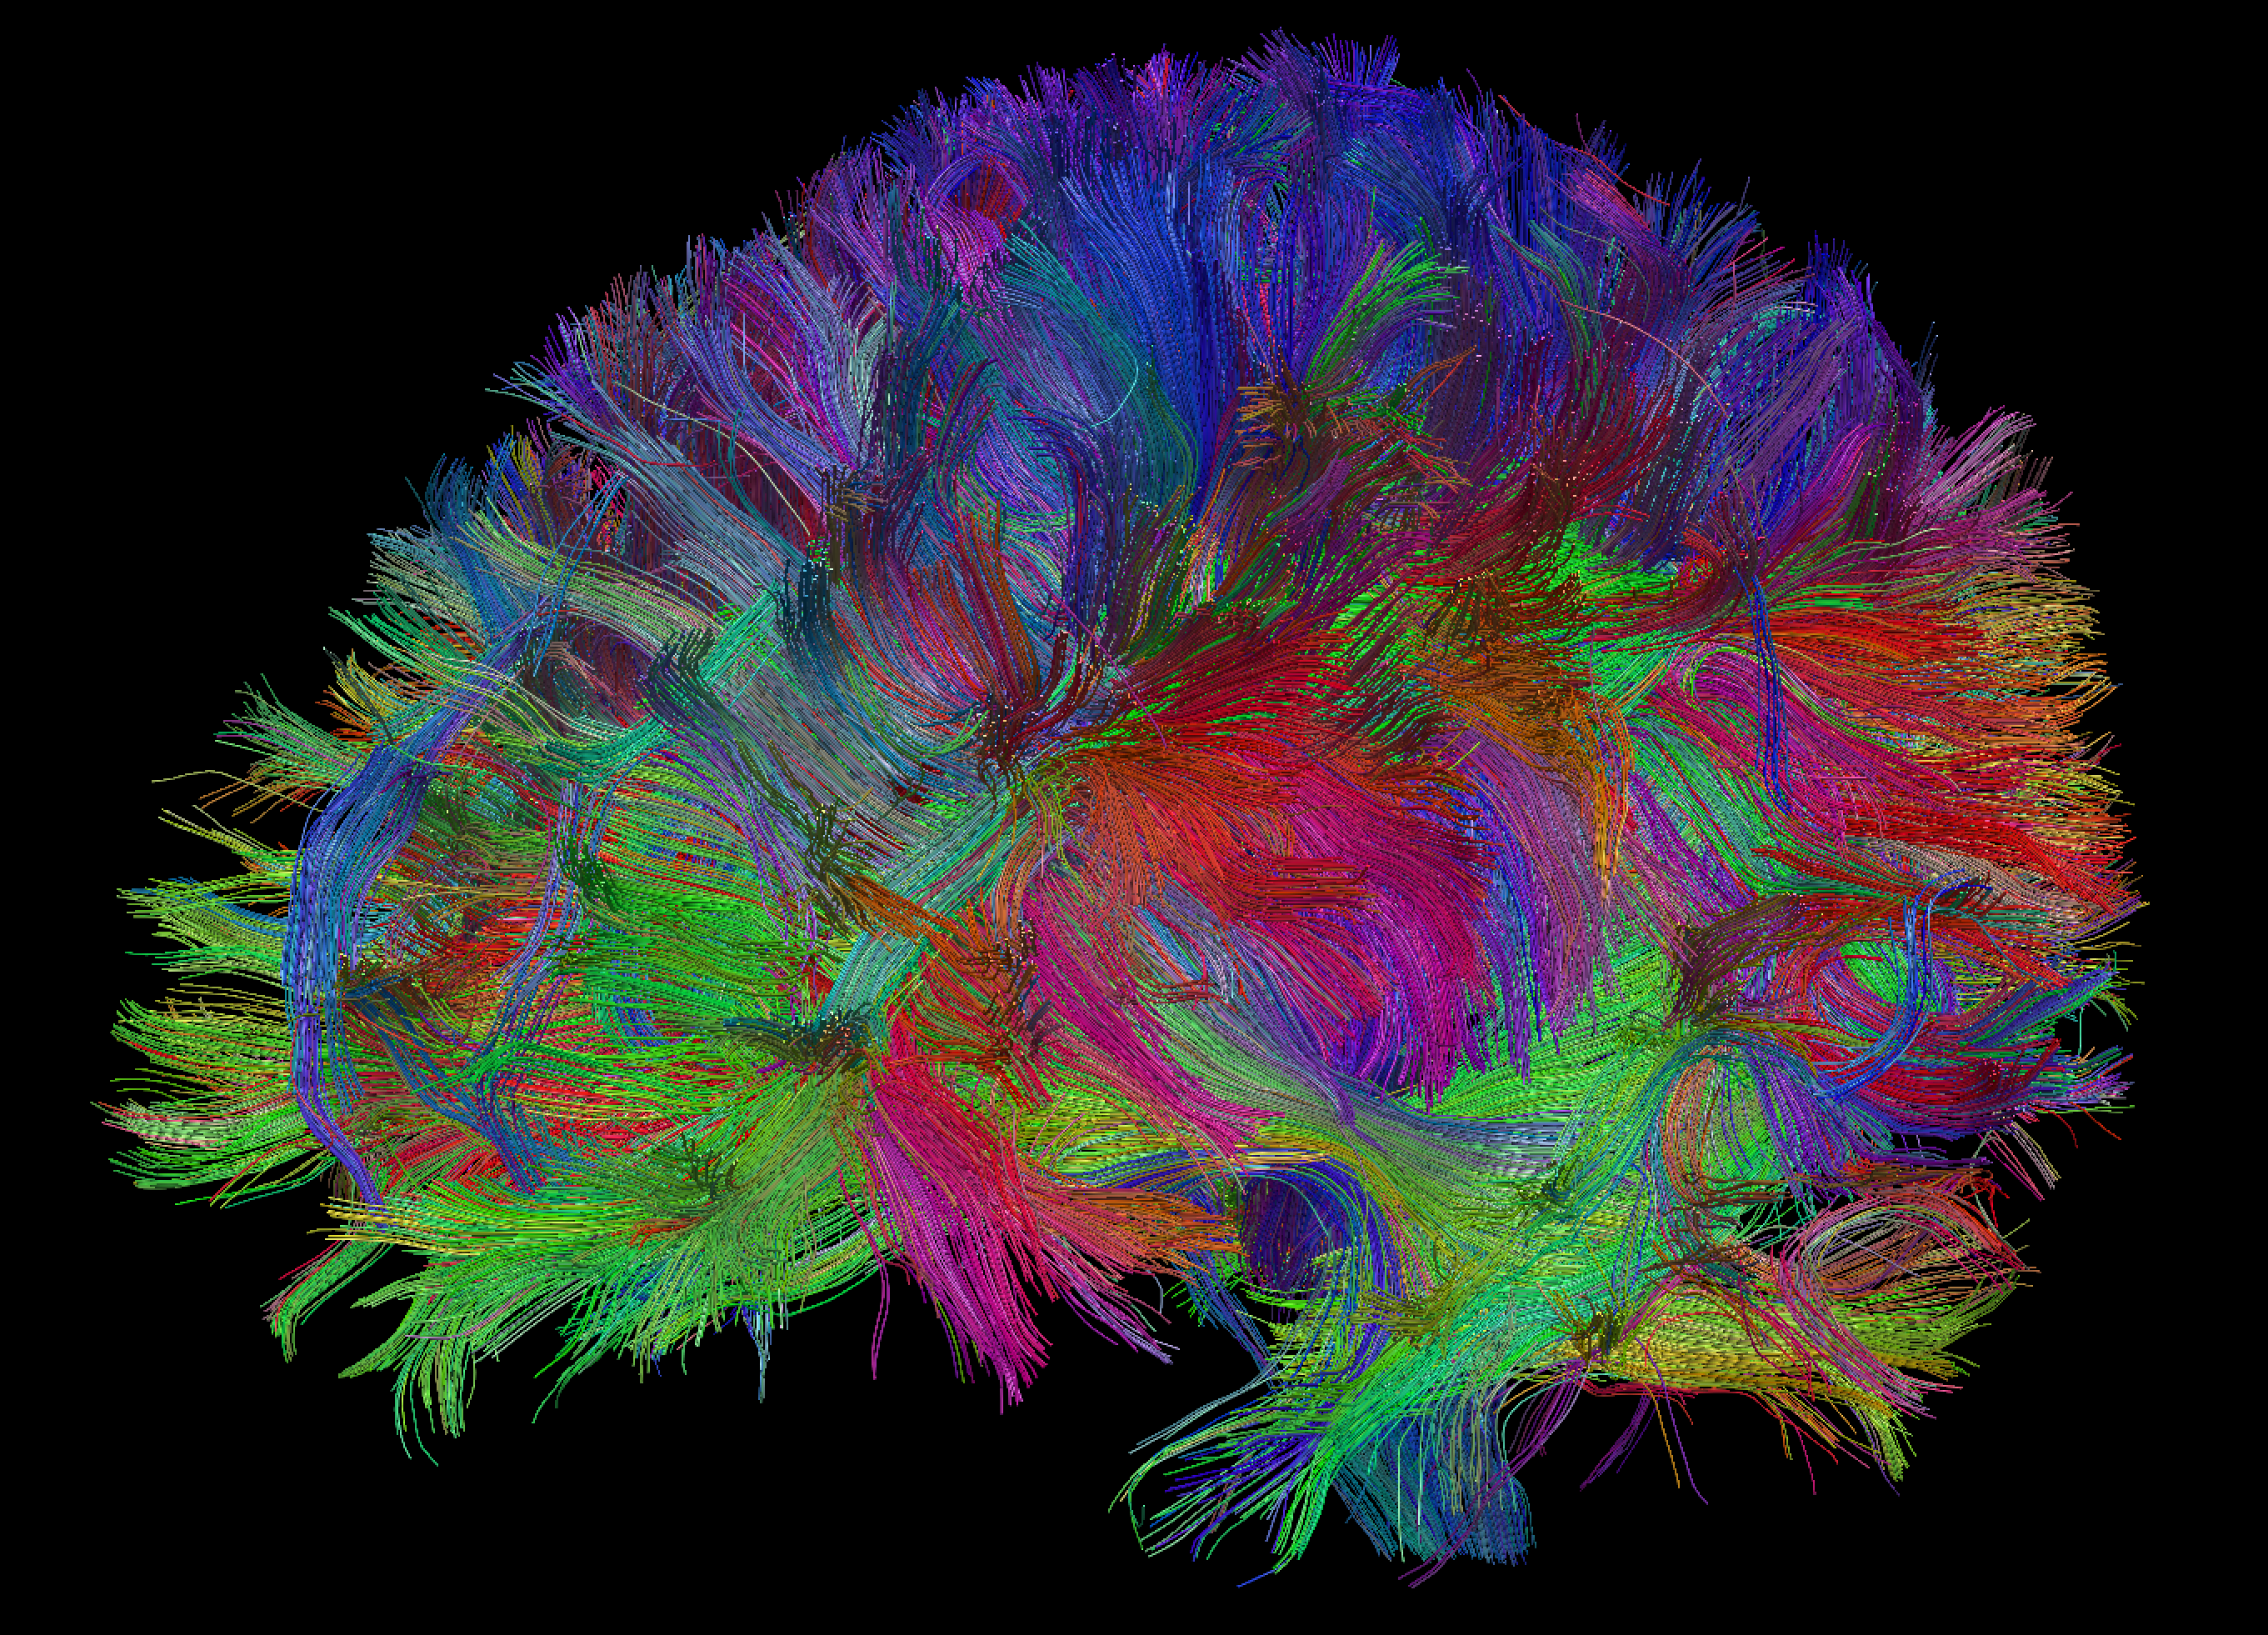

Tractography Visualizing Brain Fibers

Tractography is a visual representations of brain white matter fiber anatomy, as such, explore the next visualization to observe some neural connections before anything else.

The estimation of a fiber tract is based on the Tensor information, so to construct a single fiber, it’s necessary to start from a predefined voxel (seed) and start connecting adjacent voxels in a manner that represent the fiber trajectory. A deterministic [1] or probabilistic [2] approach may be used to select the next voxel to be added.

The visualization below is an extraction from the above, but only fibers bigger than 70mm in length are displayed. It’s easier to observe the connections from both hemispheres and the extent of some lateral fibers.

Tractography is a valuable tool for neurosurgery planning and evaluation, it is an open research area, where new methods are being developed and improved. Machine Learning Algorithms, Artificial Fibers and Fast Rendering Techniques are some of the most promising technologies that may increase even more this important visual tool.